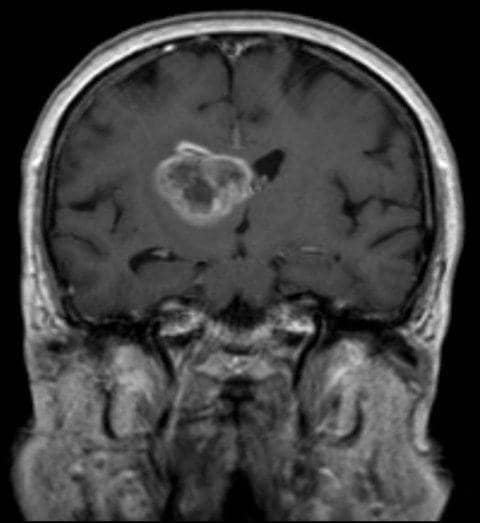

Glioblastoma merupakan jenis tumor yang menyerang sel otak dan tumbuh pada salah satu sisi otak. Tumor ini terbentuk dari sel berbentuk bintang di otak yang disebut, astrosit. Sekitar satu dari lima tumor yang dimulai di otak adalah glioblastoma ini. Menurut National Brain Tumor Society Amerika, angka harapan hidup rata-rata dari penyakit ini adalah 15 bulan hingga 3 tahun setelah didiagnosa.

Glioblastoma dikategorikan sebagai tumor ganas dan agresif karena perkembangan sel-sel tumor ini sangat cepat. Oleh karena itu tumor ini bisa sulit untuk diobati karena dalam tumor terdapat banyak jenis sel-sel abnormal yang berbeda-beda, yang mana sebagian dapat merespon dengan baik pada terapi tertentu dan sebagian sel lainnya tidak.